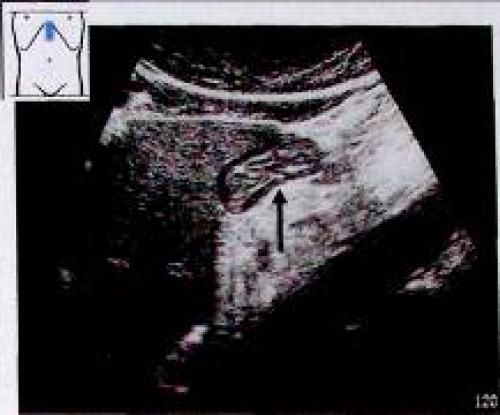

Далеко не всегда удается выделить пять слоев стенки желудка. Как правило, лучше всего виден срез антрального отдела желудка, зачастую же видны только три слоя: гиперэхогенные внутренний и наружный слои и гипоэхогенный средний слой. Датчик располагают в верхнем левом квадранте живота. У пациентов натощак слои стенки антрального отдела желудка могут быть видны позади печени и непосредственно перед поджелудочной железой. Тень от воздушного пузыря мешает адекватному обследованию пациентов с метеоризмом или после приема пищи. Если желудок значительно растянут, необходимо искать опухоли стенки или утолщение стенки как проявление гипертрофии пилорического отдела. В зависимости от степени сокращения, стенка желудка должна иметь толщину 5—7 мм, и гипоэхогенный мышечный слой в ней не должен превышать 5 мм. Любые подозрения на поражение стенки желудка следует разрешить последующей гастроскопией или рентгенографией.

Для точной оценки слоев стенок желудка его заполняют 500 1000 мл чая или воды (заглатывается через соломинку). При необходимости внутривенно может быть введено 20 мл бутилскополамина (гиосцина бутилбромид).Используется датчик: 5,0 МГц. Датчик 3,5 МГц лучше использовать для обзорных снимков, в особенности для оценки задней стенки и дна желудка. Пациент обычно находится в положении лежа на спине, однако иногда используются специальные положения.

На аппарате с высокой разрешающей способностью и при благоприятных условиях обследования иногда удается выделить пять слоев стенки желудка (1):

- гиперэхогенная граница между полостью и слизистой оболочкой;

- гипоэхогенный мышечный слой слизистой оболочки;

- гиперэхогенная подслизистая оболочка;

- гипоэхогенная мышечная оболочка;

- гиперэхогенная наружная граница серозной оболочки.

Рис. 1. Послойное строение стенки желудка (^).